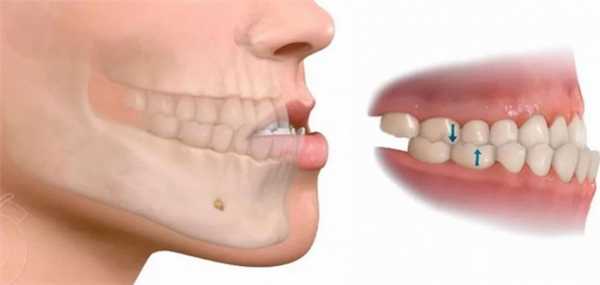

Прикусом называют взаимоотношение нижнего и верхнего зубных рядов при полном смыкании и максимальном контакте. Это первый параметр, который оценивает грамотный ортодонт у ребенка или взрослого. Базовые проблемы с прикусом можно определить даже на глаз: врачу достаточно попросить пациента сомкнуть зубы.

Существует правильный (нормальный, физиологический) прикус, при котором нагрузка на зубы приходится равномерная, и патологический. Неправильный прикус может сформироваться в любом возрасте из-за разных факторов. Он сильно влияет на организм и общее состояние человека.

Каким должен быть прикус у человека

Физиологический или нормальный прикус имеет следующие признаки:

- все зубы верхней и нижней челюсти контактируют между собой, причем каждый зуб смыкается с двумя антагонистами. Исключение — третий верхний моляр и первый нижний резец;

- срединная линия лица проходит между центральными резцами;

- отсутствуют промежутки между отдельными элементами рядов;

- верхняя зубная дуга имеет форму полуэллипса, нижняя — параболы.